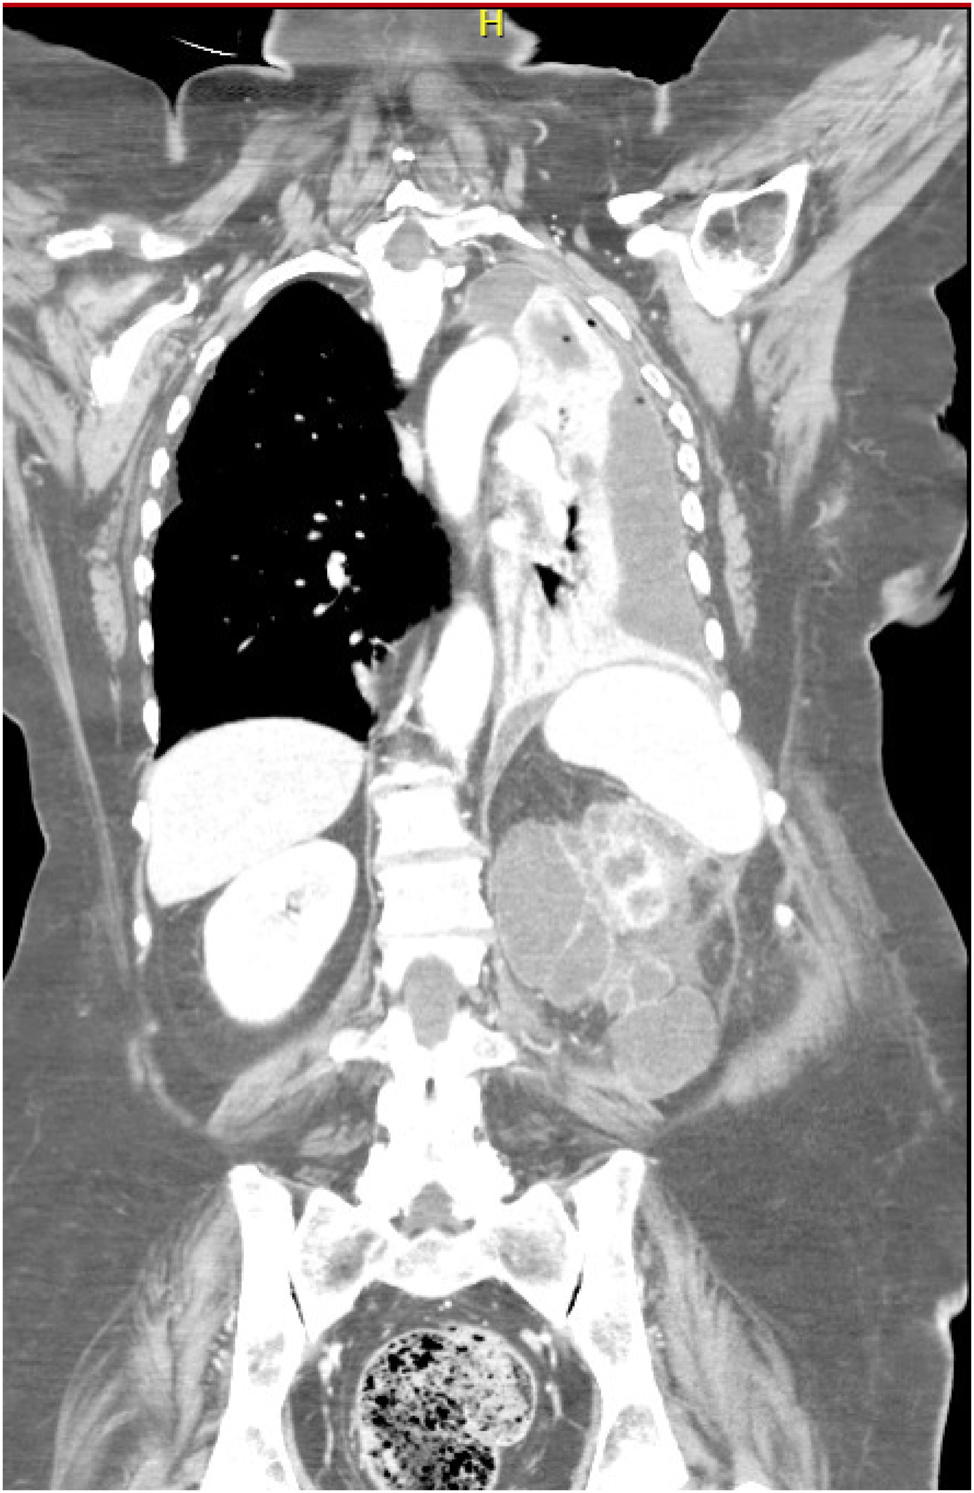

A 73 y-o female patient was referred to “MG Vannini” Hospital in Rome with a complaint of dull persistent left flank pain with intermittent sciatica, general malaise, dysuria, and fever (39 °C): initially, the patient was normotensive but exhibited tachycardia (130/min) and then rapidly, during the first hospitalization hours in Emergy Room, developed respiratory distress and sepsis with drowsiness, hypotension and tachypnea. Blood tests showed leukocytosis (14.3 103/mm3, normal value 4.0–10.0), thrombocytosis (PLT 525 103/mm3, normal value 140–400), increased fibrinogen (>900 mg/dL, normal value 150–400), and C-reactive protein levels (17.0 mg/dL, normal value 0.0–0.5); blood gas analysis in ambient air patient breathing showed pH=7,24, pCO2=50,3 mmHg, pO2=73,7 mmHg, O2 saturation 93 %. This results were compatible with a septic state. Renal function was normal so patient underwent a contrast medium whole body CT scan which showed left pleural empyema (35 mm maximum thickness) associated with ipsilateral lung complete atelectasis and left main bronchus caliber abrupt reduction (Figure 1); the abdominal imaging showed the left kidney with a widespread parenchymal density alteration with reduction of the cortico-medullary boundary, multiple nephrolithiasis even at upper ureter level, with perinephric mostly retro-renal abscess collections (maximum diameter 43 mm), which seem to communicate with the left pleural cavity through a trans-diaphragmatic fistula (Figure 2). The right kidney was normal in shape and excretory function: no left-kidney contrast medium elimination was shown. Chest drain was inserted by Seldinger technique under direct ultrasound guidance obtaining 200 mL of purulent material which resulted in partial respiratory improvement, even if an oxygen supplementation was still required; the perirenal abscess was also drained percutaneously and a broad spectrum intravenous antibiotic was administered (Meropenem 1,000 mg every 8 h). Microbiology specimens from the pleural and perinephric fluids grew Klebsiella pneumoniae which was treated with Piperacillin and Levofloxacin based on culture sensitivity. Starting from the fourth hospitalization day, with empirical antibiotics in progress and therefore before applying the appropriate culture responses-based treatment, patient’s respiratory conditions improved (pH 7.36, pCO2 46.4 mmHg, pO2 91.8 mmHg, O2 saturation 95 %), as did the inflammation (leucocytes=11.2 103/mm3, C-reactive protein levels=13.0 mg/dL); however, a further CT scan showed the pleural empyema and perirenal collection persistence, also reported by the drainage positivity, leading us to proceed with a combined urological-thoracic surgery. With patient’s left side up, at 90° on the operating table to allow simultaneous thoracic approach without changing position, a retroperitoneoscopic left nephrectomy with a wide extra-gerotal dissection was performed; in between the upper pole and left diaphragm a huge pus collection and a trans-diaphragmatic fistula were appreciable, confirming CT findings. The fistulous tract was excised and the diaphragm was closed with 0-0 absorbable interrupted stitches; the retroperitoneoscopy was performed using a valvelss-trocar system (AirSeal®), pre-setting the CO2 pressure between 8 and 10 mmHg thus avoiding increased CO2 absorption and higher end-tidal CO2 and PaCO2, resulting in reduced venous flow and respiratory compliance. These biochemical, vascular and respiratory alterations commonly observed in conventional CO2 insufflation, both with trans-peritoneal and retroperitoneal approach, may be potentially harmful events in one case like ours; moreover the retroperiteoscopy avoided excessive diaphragmatic fibres distension, thus reducing the intrathoracic compression which would have limited the already reduced pulmunary expansion. Even though the working space was small especially in the fistulectomy and diaphragmatic closure phase, the retroperitoneoscopic experience gained over the years by the urology team allowed the operation to be completed without complications, using two straight needle holders and a 2/0 absorbable suture with interrupted stitches. Once the kidney has been removed and complete retroperitoneal cleaning and fistulectomy have been carried out a VAT surgery to decorticate pleural cavity and lung surface was performed by the thoracic surgery equipe. No intraoperative complications were observed; renal histology revealed XGP and renal stones, with multiple renal abscesses. Patient was discharged in 7 post-op day. At time, after one year, patients has not presented infectious pleural/retroperitoneal recurrecences.

Preoperative thorax-abdomen contrast-enhanced CT, showing left pleural empyema (35 mm maximum thickness) associated with ipsilateral lung complete atelectasis and left main bronchus caliber abrupt reduction.